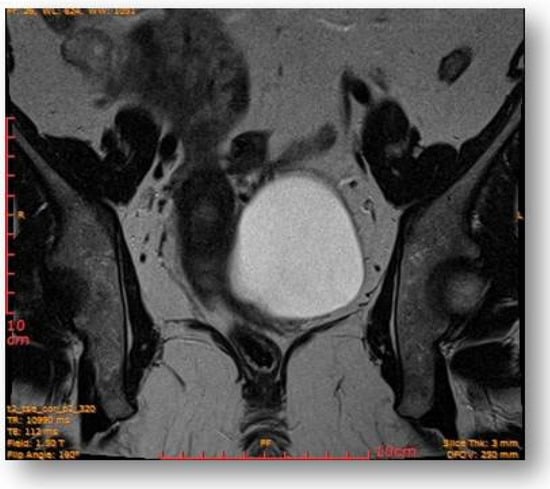

Left parauterine, between the left lateruterine wall and the left ovary, was attached to the anterior contour of the uterine round ligament, and an ovoid cystic lesion of approximately 100/68/50 mm (oblique CC/AP/LL) is evident (Figure 5).

Left parauterine, between the left lateruterine wall and the left ovary attached to the anterior outline of the round ligament, an ovoid cystic lesion of 100/68/50 mm is evident.

This showed probably proteinaceous fluid content and mildly irregular wall thickness up to ~4–5 mm (on the right lateral contour) and with a mural micronodule of ~5 mm with contrast uptake at the level of the left antero-lateral contour. The appearance advocated the first hypothesis for a “border-line” left paraovarian cyst, with suspicious elements of neoplastic transformation (Figure 6). It presented the following relationships: anteriorly, it imprints the anterior median-paramedian left pelvic wall, posteriorly with the uterine round ligament, urinary bladder, medially (to the right) with the uterus and urinary bladder, laterally (to the left) with the left ovary.

Ovoid cystic lesion imprints the urinary bladder without invasion into it.

The rectal ampulla did not show suspicious tumor masses. Several infracentimetric pelvic lymph nodes, without specific character, were noted, as well as a minimal plate of intrapelvic fluid with a millimeter thickness. No notable collections in the pelvic recesses. No suspicious focal bone lesions were evident in the pelvis on the acquired images. Diastasis of the rectus abdominis muscles in the pelvic region (distance of about 30–35 mm) could be observed (Figure 7 and Figure 8).

Ovoid cystic lesion proteinaceous fluid content and mildly irregular wall thickness up to ~4–5 mm.

Ovoid cystic lesion in the left part of the uterus.